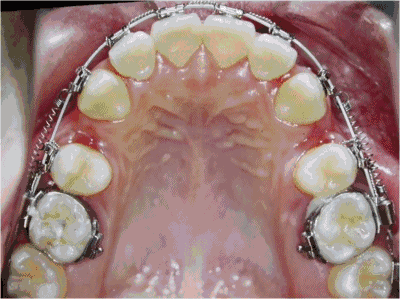

而获取间隙的方法无外乎是减数(拔牙)、减径(片切牙缝)、扩弓(扩展狭窄的牙弓)此外还有推磨牙向后。

(图片来源于网络)